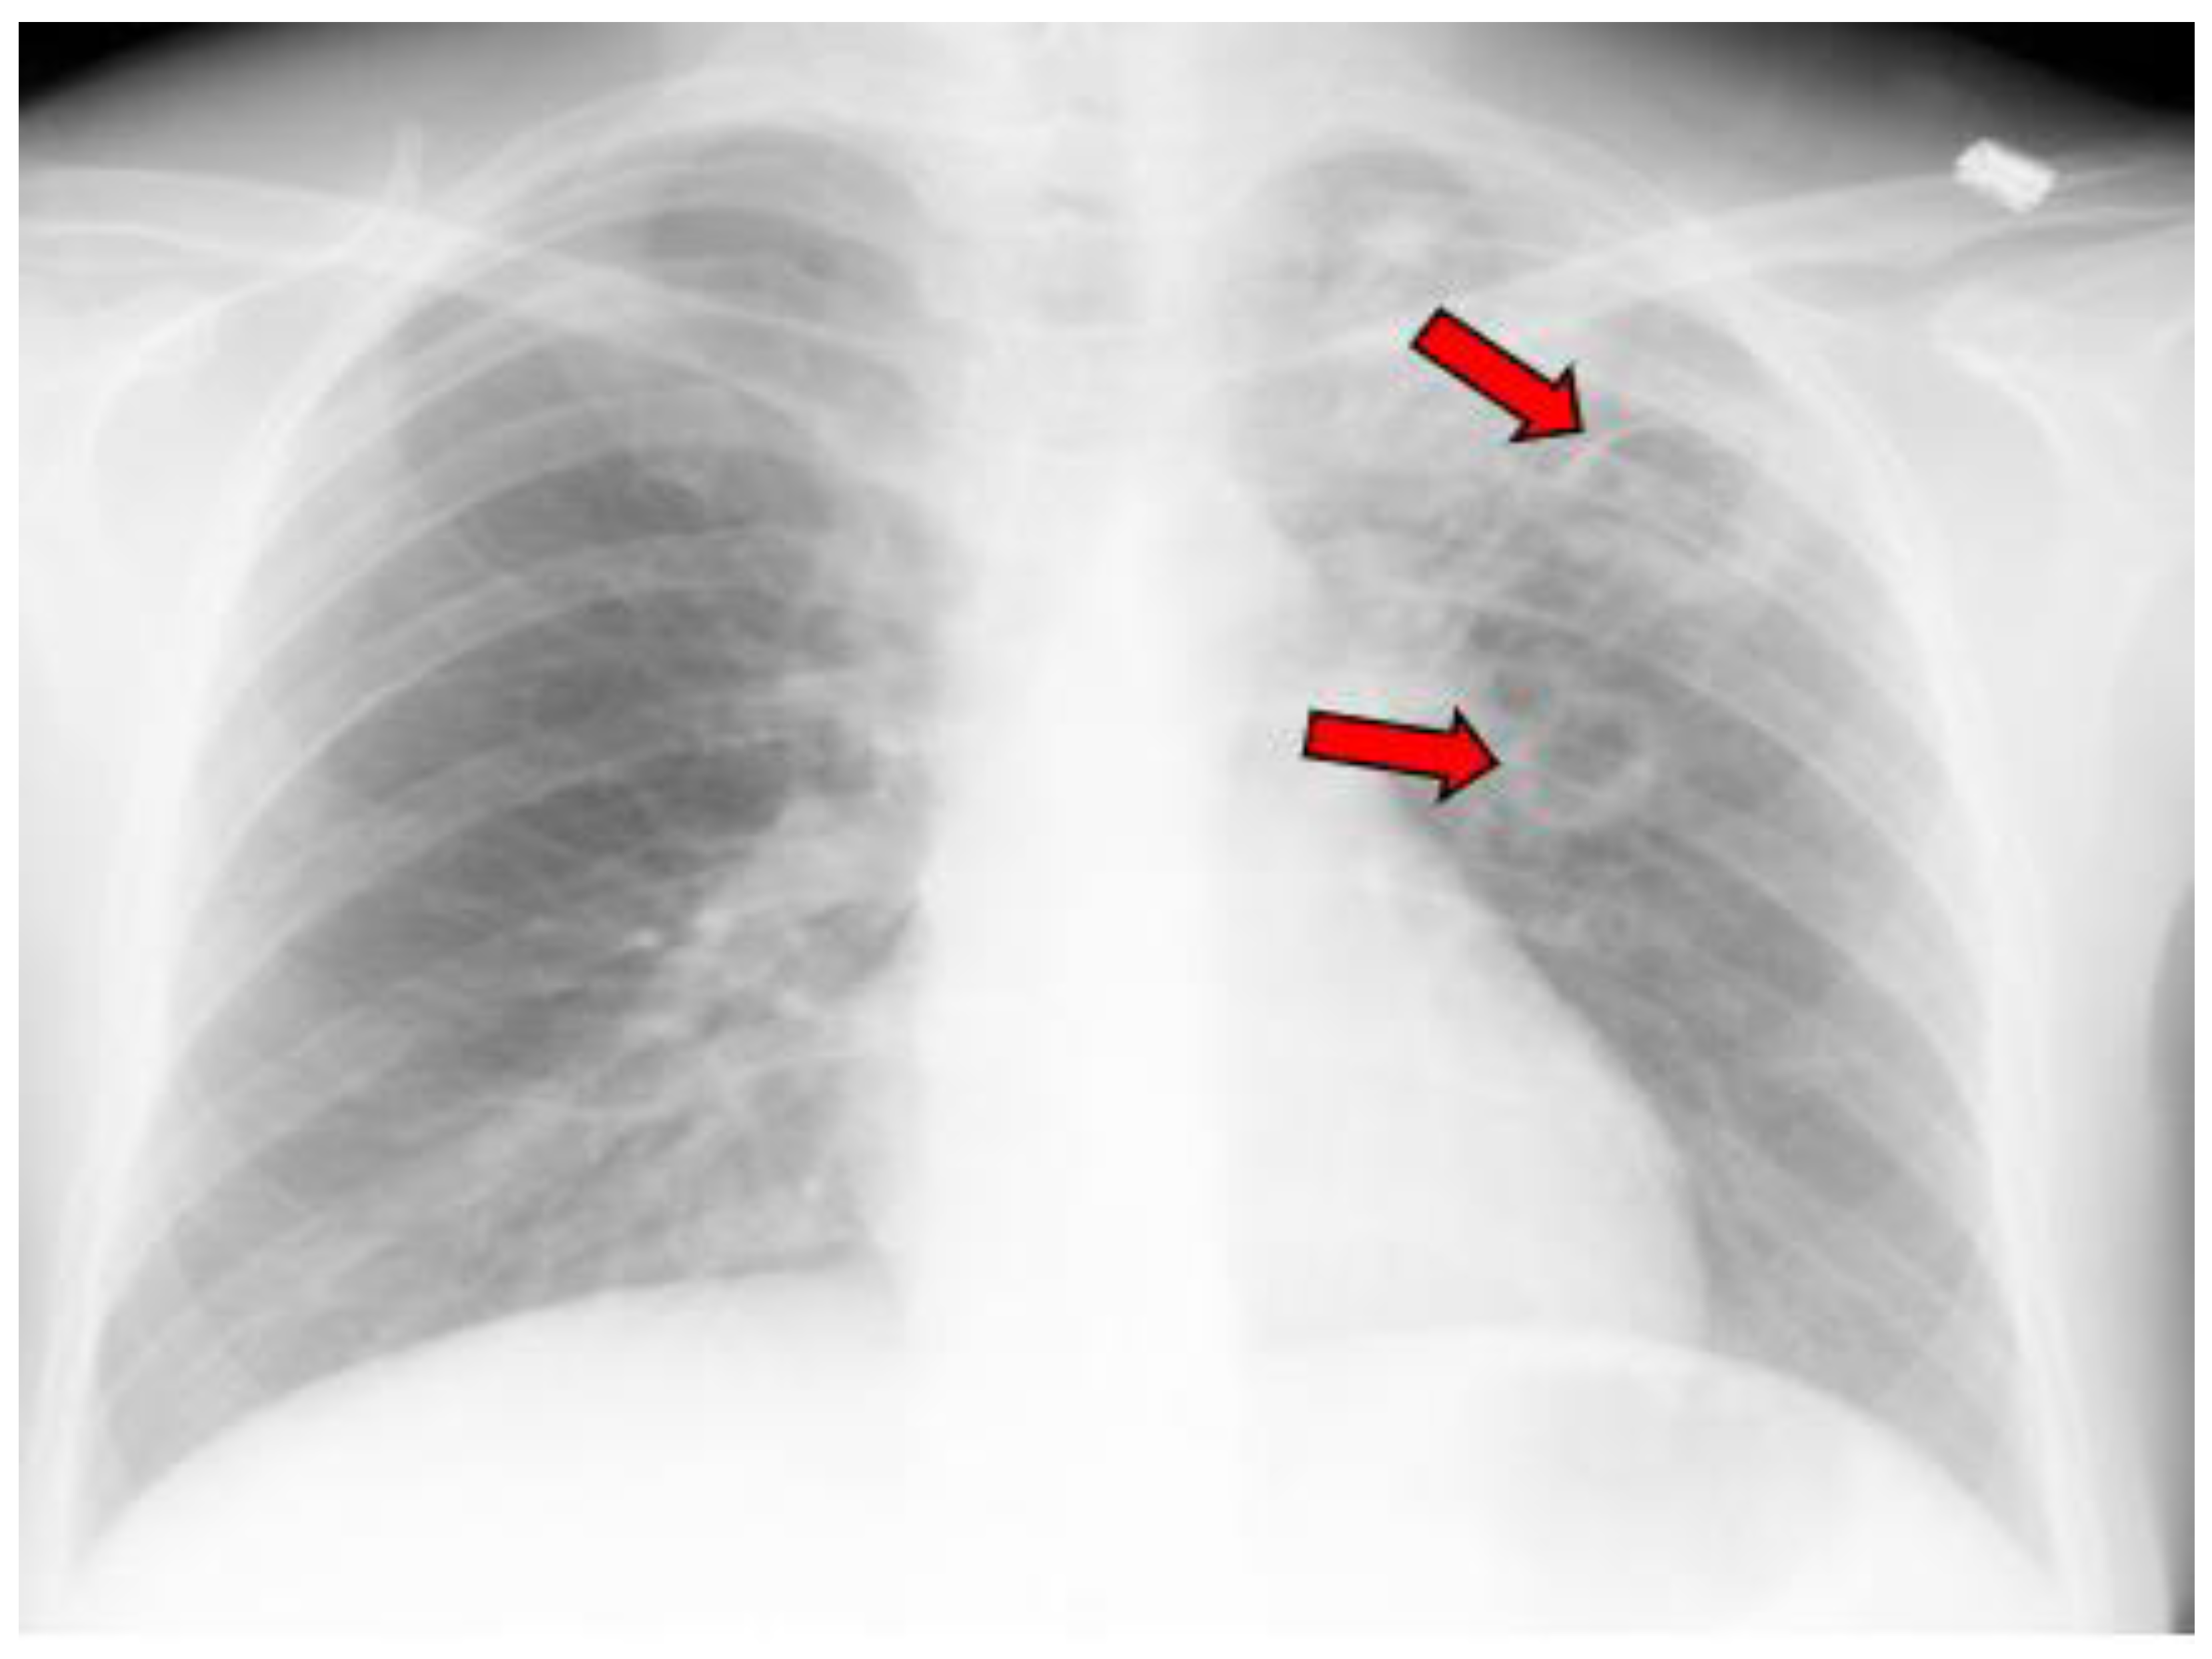

- Radiographic evidence of cavitary lesion(s) with or without concurrent infiltrative disease;

- Simple cavity and location *;

- Multiple cavities and locations *;